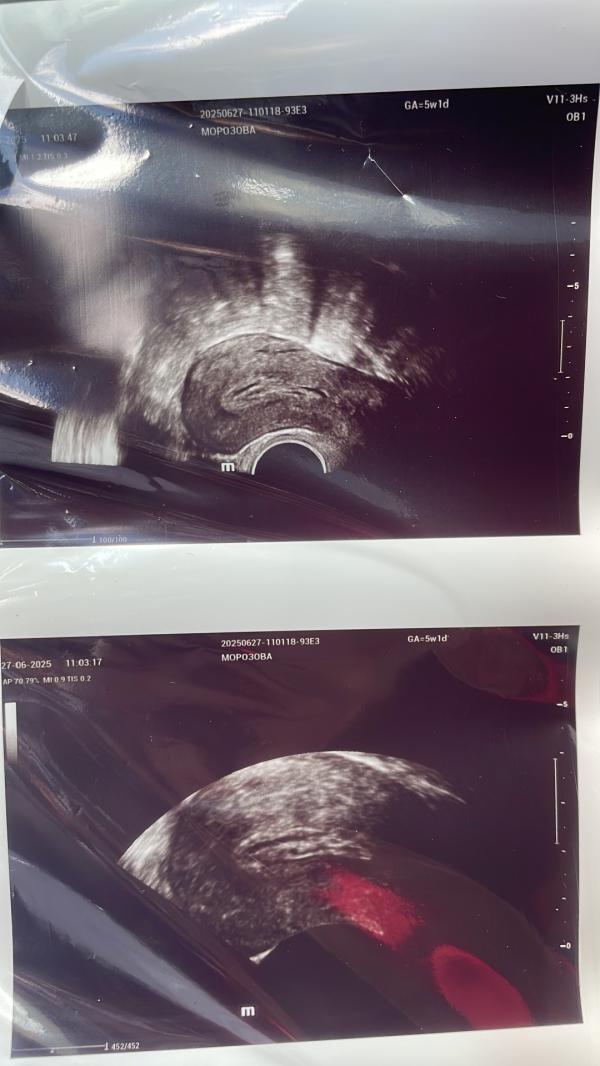

В общем похоже на неразвивающуюся беременность,так как плодное яйцо вообще не на 5 недель,что-то в полости матки есть но не то что должно,сказали отменять все препараты и должно все само выйти как месячные.

@m.ma, желтое тело хорошее

В сочетании с неоднородным эндометрием

Просто беременность может еще не визуализироваться